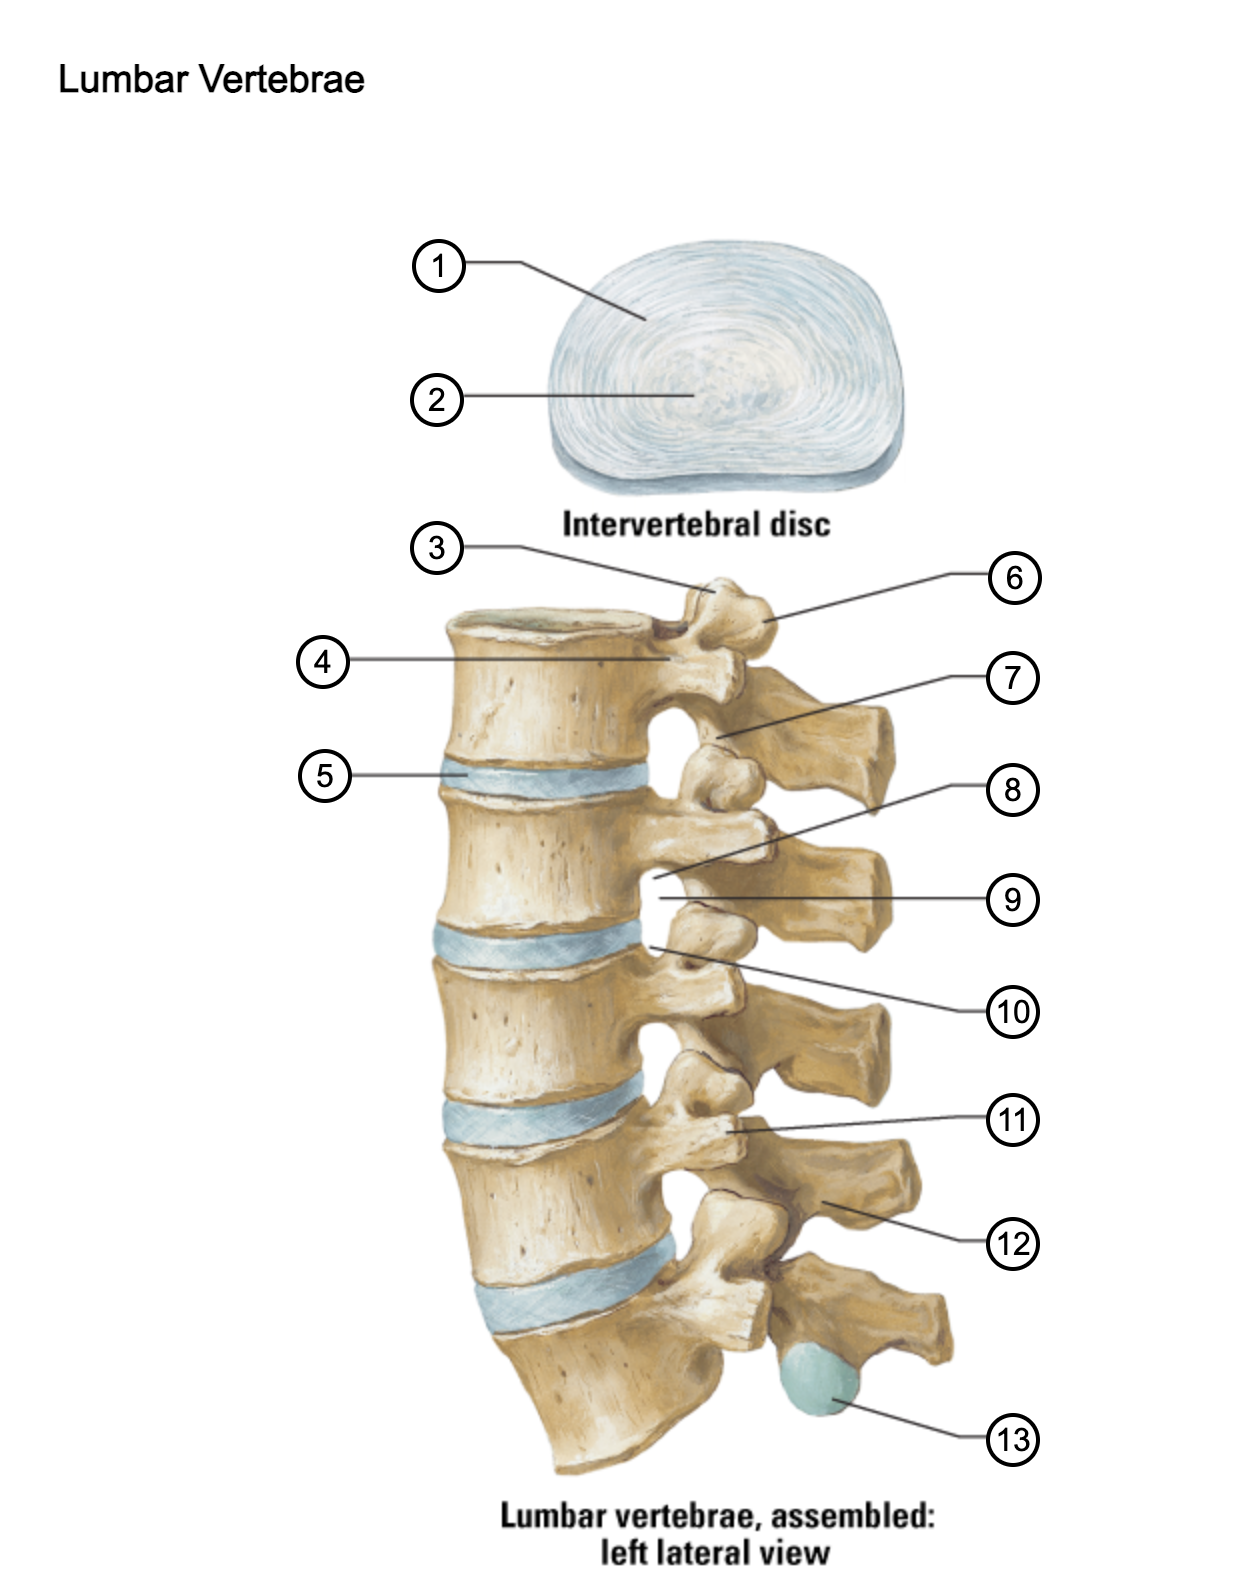

1

anulus fibrosus

2

nucleus pulposus

3

superior articular process

4

pedicle

5

intervertebral disc

6

mammillary process

7

inferior articular process

8

inferior vertebral notch

9

intervertebral notch

10

superior vertebral notch

11

transverse process

12

lamina

13

inferior articular facet